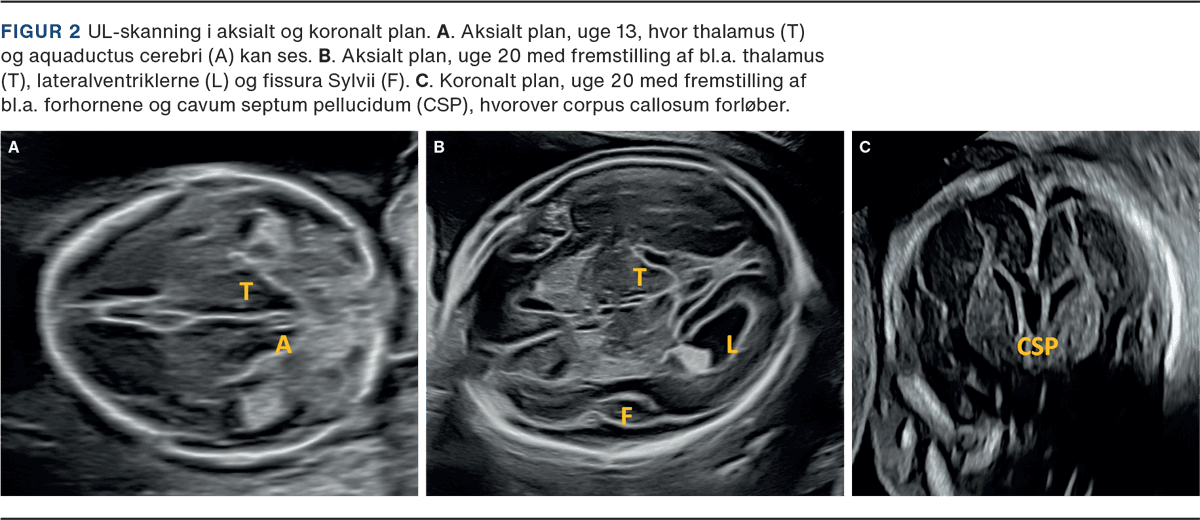

UL-skanning i 1. trimester foretages i graviditetsuge 11-14 og udføres som udgangspunkt med 2D-abdominalskanning. Ved behov kan der suppleres med vaginalskanning og evt. 3D-skanning. CNS vurderes i et midt-sagittalt og aksialt plan, hvor følgende visualiseres: intakte kranieknogler med henblik på at udelukke akrani og store encefaloceler, midtlinie og symmetriske hemisfærer og lateralventriklerne udfyldt af plexus choroideus. Der måles biparietaldiameter for at sikre intakt kranium og overensstemmelse mellem crown-rump-length og caputs størrelse. Columnas udseende og form vurderes for at udelukke alvorlig columnadefekt [5, 6]. Ud over de strukturer, der er obligatoriske at fremstille ved rutineundersøgelsen, kan man nu ofte allerede i 1. trimester visualisere thalamus, cerebrale pedunkler, aquaductus cerebri, plexus choroideus, hjernestammen, cisterna magna og tredje og fjerde ventrikel (Figur 1 og Figur 2) [5].

Ved UL-skanning i 2. trimester, som foretages i 18.-20. graviditetsuge, undersøges kraniet, de cerebrale strukturer, ansigt og columna/spinalkanal. Der foretages vurdering i tre planer, hvorved strukturer, som er væsentlige pejlemærker for normal udvikling af hjernen, visualiseres (Figur 3). Såfremt strukturerne ikke kan fremstilles normale, vil det medføre mistanke om abnorm udvikling af CNS. F.eks. er ventrikulomegali en hyppig markør for abnorm cerebral udvikling, manglende cavum septum pellucidium kan være et indirekte tegn på en række alvorlige midtlinjedefekter, som holoprosencefali og corpus callosum agenesi [8]. I op mod 96% af tilfælde med åben spina bifida vil der være abnorm facon af kraniet (lemon sign) og cerebellum (banana sign) [9].